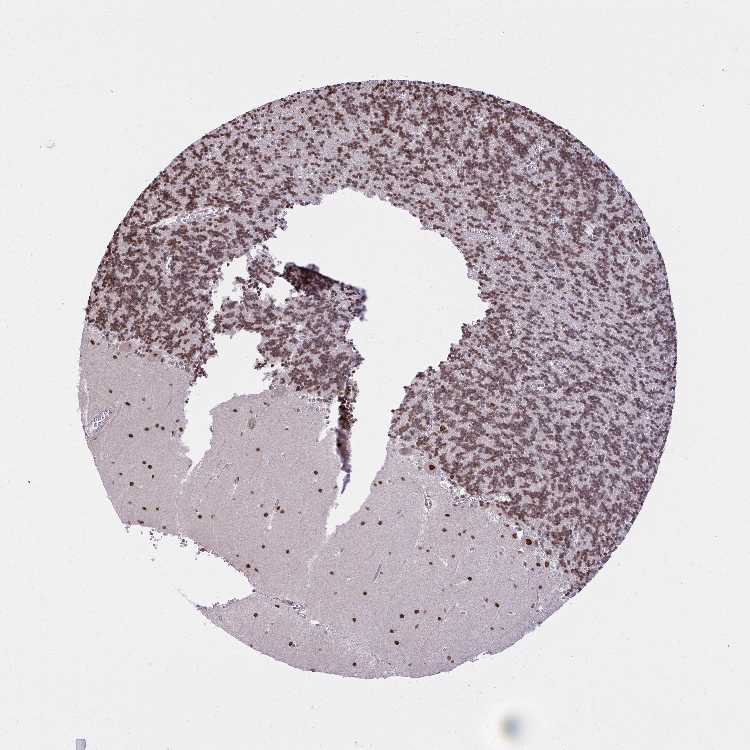

CEREBELLUM - Antibody stainingi

Antibody staining in the annotated cell types in the current human tissue is reported as not detected, low, medium, or high, based on conventional immunohistochemistry profiling in selected tissues. This score is based on the combination of the staining intensity and fraction of stained cells.

Each image is clickable and will lead to virtual microscopy that enables deeper exploration of all samples and also displays staining intensity scores, fraction scores and subcellular localization as well as patient and tissue information for each sample.

Antibody HPA059018

Purkinje cells High

Cells in granular layer Medium

Cells in molecular layer High